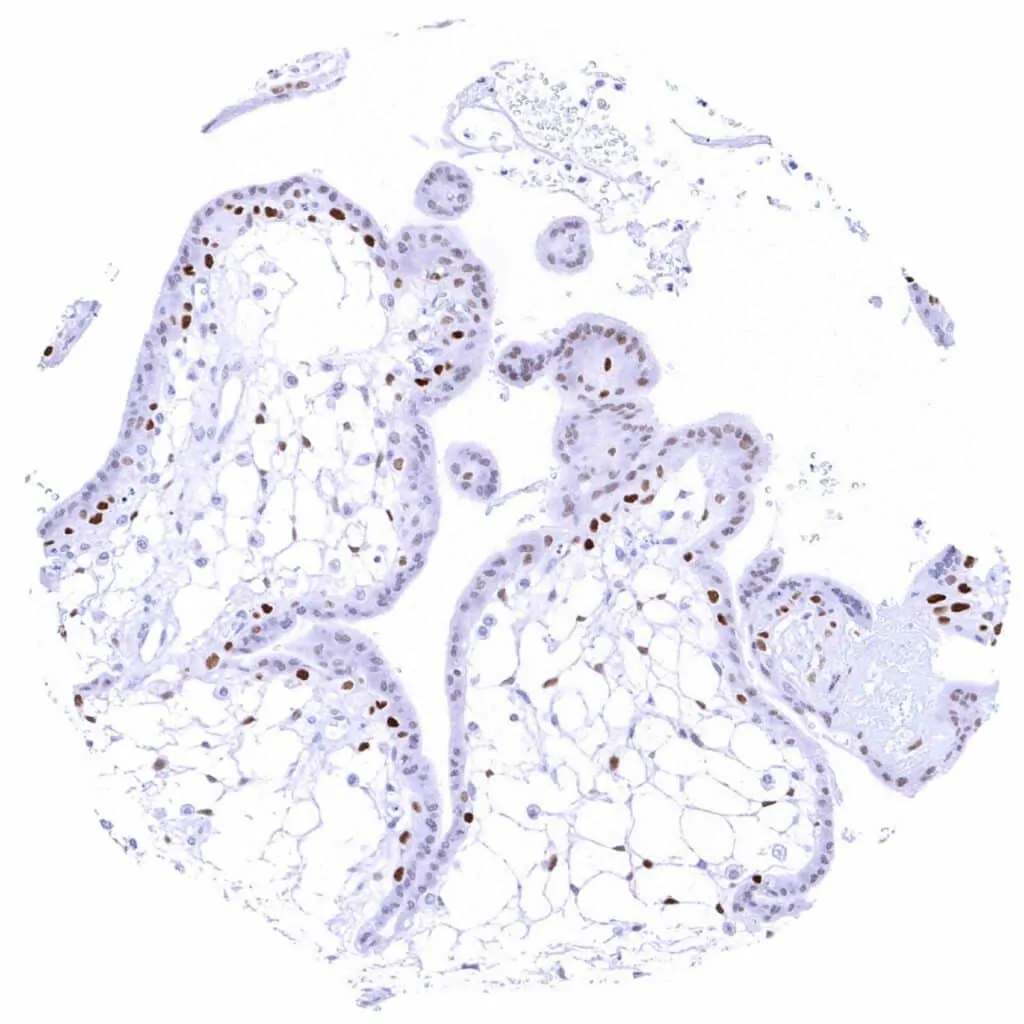

Placenta, first trimenon – Strong Cyclin E1 staining of most cytotrophoblast cells while stroma cells stain less intensively